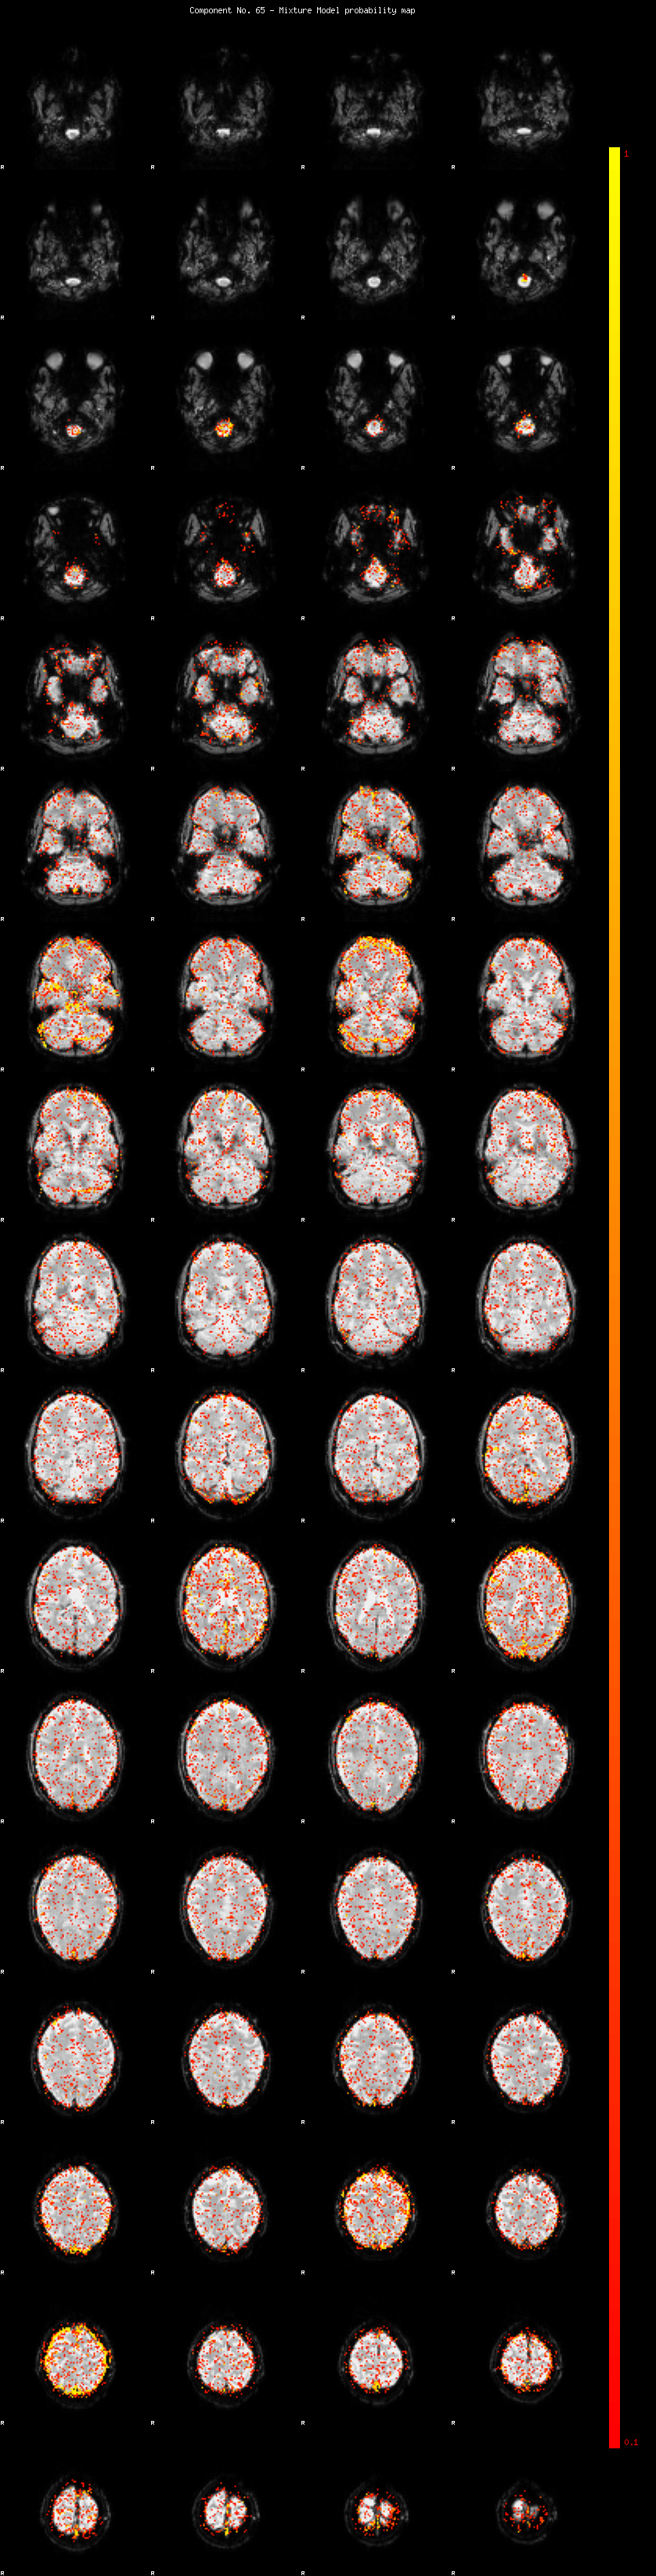

IC_65 Mixture Model fit

Means : 0.000000 2.269872 -2.286818

Vars : 1.000000 1.370954 1.175398

Prop. : 0.941010 0.035146 0.023844